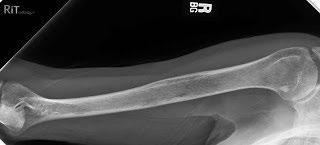

Testing To Determine A Diagnosis of Myeloma: Imaging

Imaging:

– Skeletal survey: Series of X-rays; less sensitive than other techniques

Healthy bone versus myeloma bone disease

– Whole body low dose (CTWB-LD CT )

– Positron Emission Tomography (PET/CT)

– Magnetic Resonance Imaging (MRI)

This Photo by Unknown Author is licensed under CC BY-NC-ND

Testing For Myeloma: Imaging